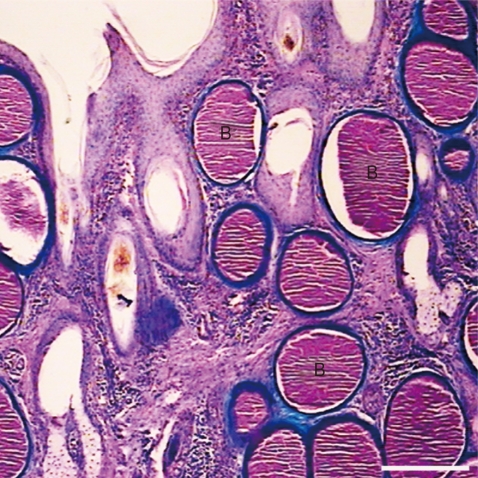

Goats with naturally occurring chronic besnoitiosis were identified by observing Besnoitia cysts in their conjunctiva and subsequent confirmation on histopathological sections of the skin covering the tarsal or carpal area (Fig. 1) [7]. Two naturally infected goats, exhibiting clinical features of caprine besnoitiosis were culled and then painlessly euthanized according to the Iranian Veterinary Organization rules. The skin and subcutaneous tissues from these animals were collected and stored at 4℃, and transported to the laboratory. To remove surface contaminations, tissue pieces were separately washed in a petri dish containing Dulbecco's modified eagle medium (DMEM) supplemented with 2% fetal calf serum (FCS), 1% antibiotic solution (10,000 IU penicillin and 10,000 mg streptomycin/ml solution) and 1% amphotericin B (250 mg/ml). Subsequently, the tissue sections were cut into 1-2 mm3 pieces with scalpel. The liberated bradyzoites was collected by spinning the DMEM at 770 g for 15 min at 4℃. The pellets were resuspended in DMEM and the B. caprae bradyzoites were counted using a Neubauer chamber. The bradyzoites were cryopreserved by resuspending in FCS containing 10% DMSO, and stored in liquid nitrogen.

Fig. 1

Besnoitia caprae tissue cysts (B) in the skin of distal parts of the leg in an infected goat. Alcian blue/PAS. ×180.

Fig. 1 Besnoitia caprae tissue cysts (B) in the skin of distal parts of the leg in an infected goat. Alcian blue/PAS. ×180.